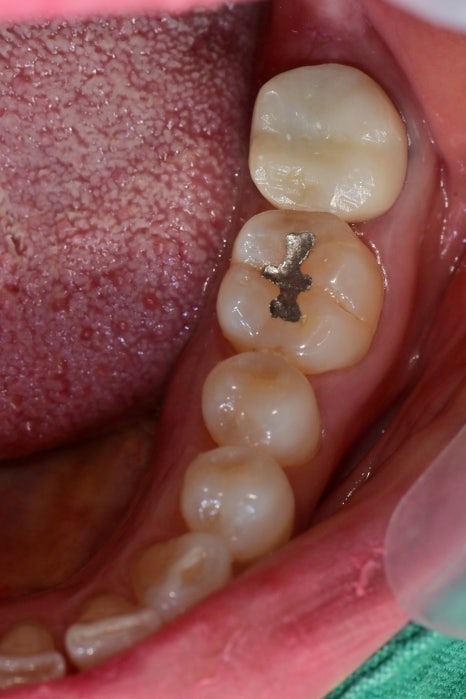

가만히 있어도 불편하고 욱씬거려요

과거에 신경치료를 하시고 크라운을 씌운 상태에서 통증을 느끼셔서 내원해 주셨습니다

엑스레이상에서 뿌리 하방으로 염증소견이 보였습니다.

근관치료를 받으신지 오래되셨고 뿌리 쪽에 기둥도 심어져있어서

재근관치료가 어려워 보였습니다.